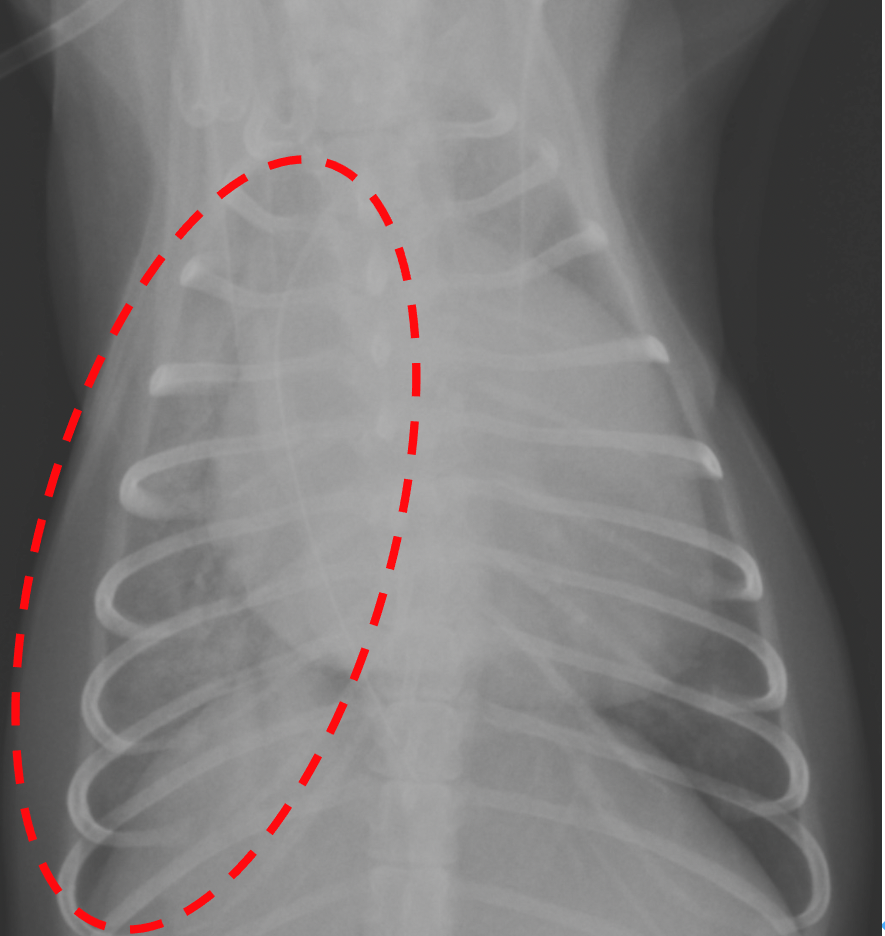

肺水腫が認められた領域(点線)が改善。